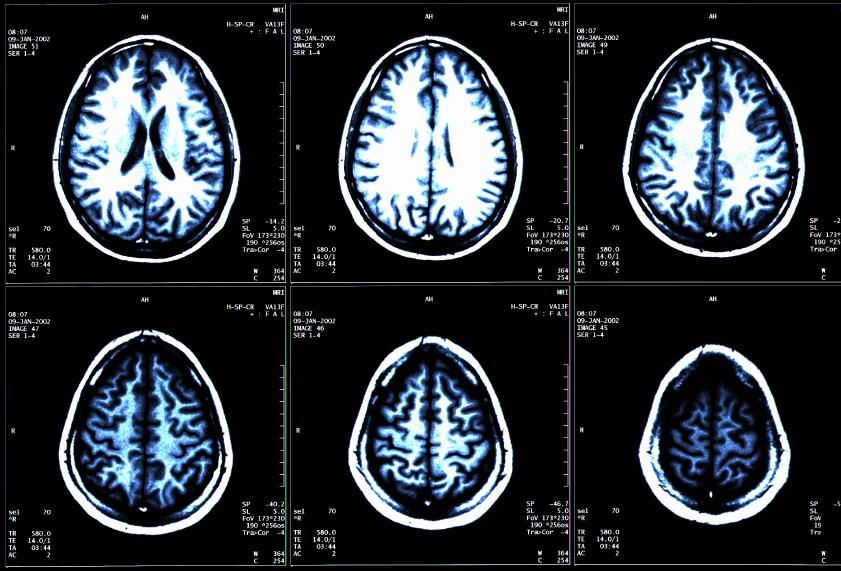

The Clinical Picture Of Multiple Sclerosis Nervous System Disorders